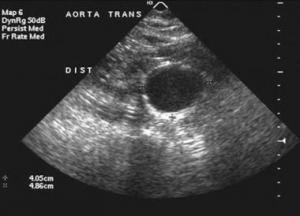

Calcification of the abdominal aortic wall is frequently evident on plain radiographs of the abdomen, as demonstrated in the images below.

In the United States, 15,000 deaths per year are attributed to abdominal aortic aneurysms (AAAs). Abdominal aortic aneurysms occur most commonly in individuals between 65 and 75 years of age.

Most clinically significant AAAs are palpable upon routine physical examination; however, the sensitivity of palpation depends on the experience of the examiner, the size of the aneurysm, and the size of the patient.